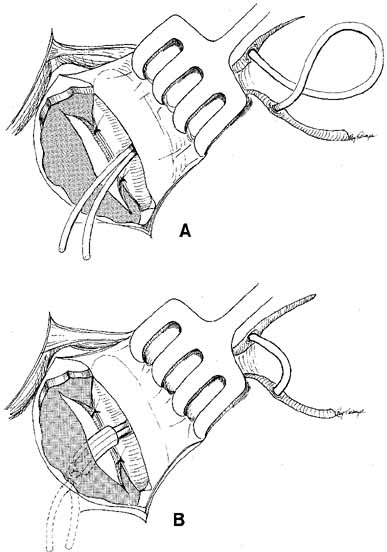

at the medial canthus.  Fig. 44 A. Silastic intubation is required after excision of scars in the area of

the common internal punctum and for moderate degrees of canaliculostenosis

or obstruction. The probes are placed through the upper and lower

canaliculi and through the common internal punctum. Any scar tissue

over this area is excised. B. The Silastic is brought down through the dacryocystorhinostomy (DCR) window

and cuffed as described earlier. This type of tubing with

a cuff will suffice as a stent in these instances, and will maintain

separation of the anterior and posterior mucosal flaps. Use of this

tubing eliminates the need for a catheter or for packing to act as a

stent. Fig. 44 A. Silastic intubation is required after excision of scars in the area of

the common internal punctum and for moderate degrees of canaliculostenosis

or obstruction. The probes are placed through the upper and lower

canaliculi and through the common internal punctum. Any scar tissue

over this area is excised. B. The Silastic is brought down through the dacryocystorhinostomy (DCR) window

and cuffed as described earlier. This type of tubing with

a cuff will suffice as a stent in these instances, and will maintain

separation of the anterior and posterior mucosal flaps. Use of this

tubing eliminates the need for a catheter or for packing to act as a

stent.